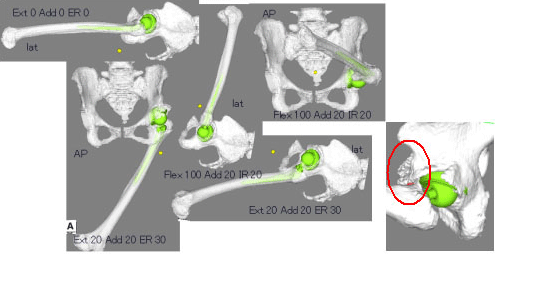

| Ⅱ: 可動域シミュレーション機能 | |

|

![]() |